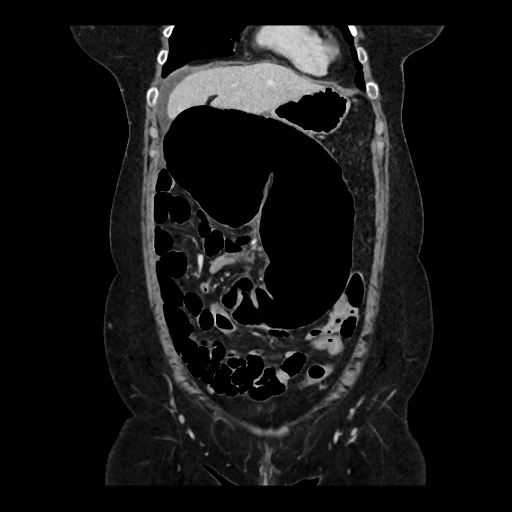

Une patiente de 59 ans, avec antécédents de lithiases vésiculaires, se présente aux urgences pour une douleur abdominale diffuse à type de colique, d'apparition brutale depuis la veille au soir. La douleur est d'intensité 8/10, sans position antalgique ni caractère transfixiant. La patiente signale que ces douleurs sont similaires à ses épisodes antérieurs de migration lithiasique biliaire. Le tableau clinique est également marqué par des nausées, six vomissements liquidiens et un vomissement biliaire à l'admission. La patiente note une inappétence ainsi qu'un épisode de selles liquides la veille. Ses antécédents chirurgicaux se limitent à une césarienne. A l'examen, la patiente est très inconfortable sans position antalgique, et afébrile (36,7°C). Les constantes vitales sont stables (TA 100/71 mm Hg, FC 83 bpm, FR 16 cycles/min, SpO2 95%). L'abdomen est souple, sensible en sus-pubien et épigastrique avec masse palpable sans défense ni détente. Les signes de Murphy et du psoas sont négatifs. Le bilan biologique révèle une légère hyperleucocytose (11,4 G/L) et une CRP à 6,8 mg/L, avec tests hépatiques normaux et des lactates à 1,2 mmol/L.